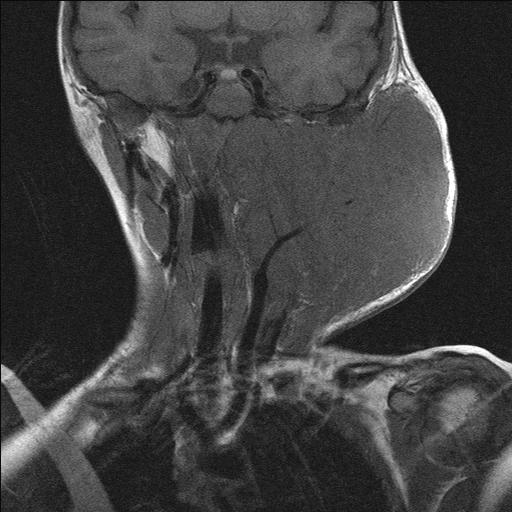

Parameningeal Head And Neck Rhabdomyosarcoma. A Axial T1-W MR Image In

Computed Tomography And Magnetic Resonance Imaging Observations Of

www.spandidos-publications.com

www.spandidos-publications.com

rhabdomyosarcoma computed tomography magnetic imaging observations resonance neck head figure ol

Computed Tomography And Magnetic Resonance Imaging Observations Of

www.spandidos-publications.com

www.spandidos-publications.com

rhabdomyosarcoma neck head embryonal axial resonance magnetic observations imaging computed tomography ol figure

Computed Tomography And Magnetic Resonance Imaging Observations Of

www.spandidos-publications.com

www.spandidos-publications.com

rhabdomyosarcoma tomography magnetic imaging computed observations resonance neck head ol figure publications spandidos